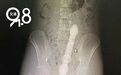

医生先做了直肠指检,指尖摸到一光滑圆锥形、粗大硬质的异物,卡在肠道内无法移动。随后马上安排腹部CT检查。

CT检查显示,小伙左下腹有一长约20多公分,粗约4-5公分,不规则的长条形异物,其上缘已到达肚脐。

图源:杭州交通91.8